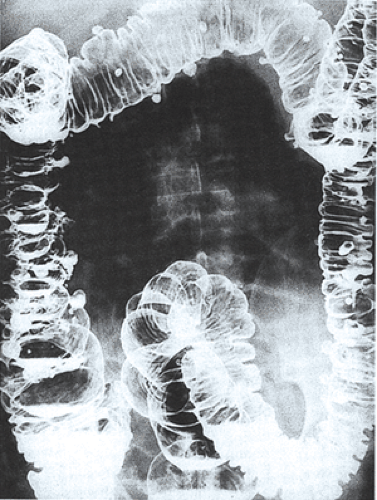

A patient presents with mild abdominal pain and fluctuating bowel habits. The barium enema image is shown below. What is your diagnosis?

Explanation: ***Diverticulosis*** - Barium enema shows characteristic **flask-shaped outpouchings** from the colon wall, representing diverticula filled with contrast. - Mild abdominal pain and **fluctuating bowel habits** are typical presentations of uncomplicated diverticulosis without inflammation. *Stricture colon* - Barium enema would show **segmental narrowing** of the colon lumen with smooth or irregular margins. - Typically presents with **obstructive symptoms** like severe cramping pain and constipation, not mild fluctuating symptoms. *Inflammatory Bowel Disease (IBD)* - Barium enema findings include **lead pipe colon** (loss of haustral markings) or **cobblestone mucosa** pattern. - Clinical presentation involves **bloody diarrhea**, weight loss, and systemic symptoms rather than mild pain. *Toxic megacolon* - Barium enema shows **massive colonic dilatation** (>6 cm transverse colon diameter) with loss of haustral markings. - Presents as a **medical emergency** with severe systemic toxicity, high fever, and signs of perforation risk.